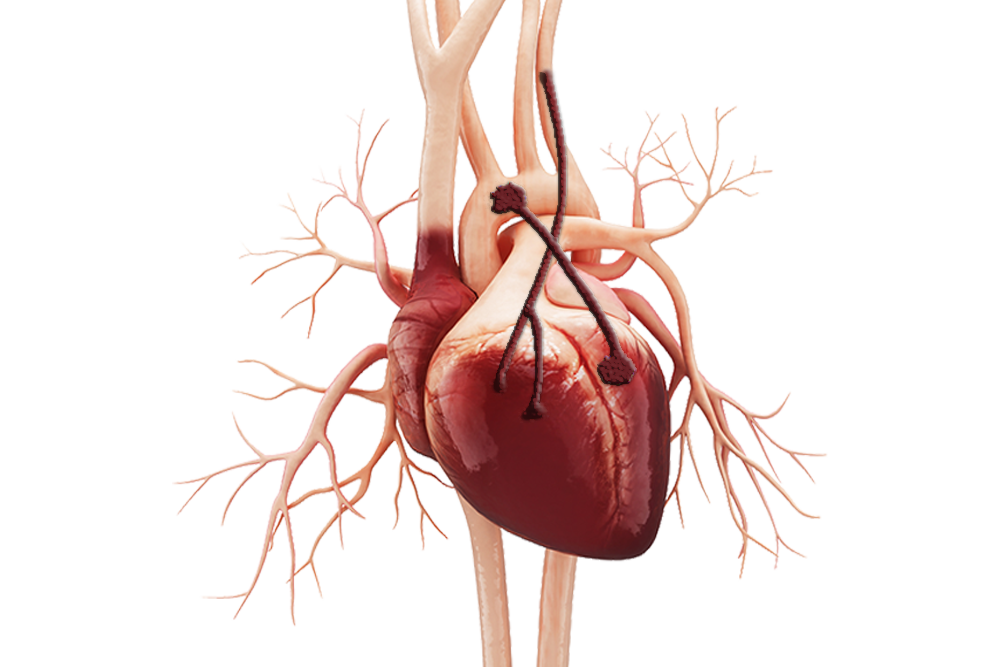

Пороки сердечно-сосудистой системы: виды и признаки